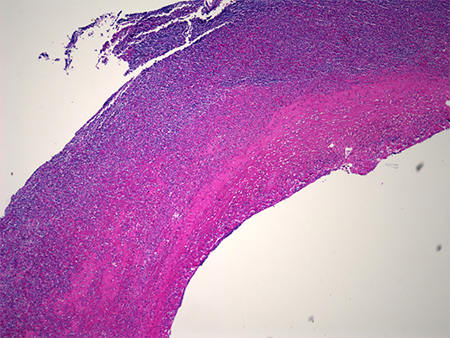

Pathology of the excised aneurysm showed a markedly dilated vessel evident of a true aneurysm, with fibrinoid necrosis and acute inflammation of the vessel wall (Figure 6). Clusters of coccus-shaped bacteria were present in the arterial wall (Figure 7).

Figure 6. Histopathology of the radial artery aneurysm. Notice the full-thickness inflammation of the arterial wall.